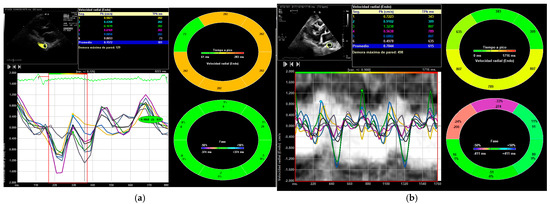

- Ruiz-Bailén, M.; Hidalgo-Martín, J.; Manetsberger, J.; Clau-Terré, F.; Martínez-Gámez, J.; Dagomar Lohman, J.; Lavilla-Lerma, M.L.; Matallana-Zapata, D.F.; Ballesteros-Barroso, M.; Rivera-Fernández, R.; et al. Usefulness of vector velocity imaging in the descending thoracic aorta. Med. Intensiv. Engl. Ed. 2025, 502224. [Google Scholar] [CrossRef]